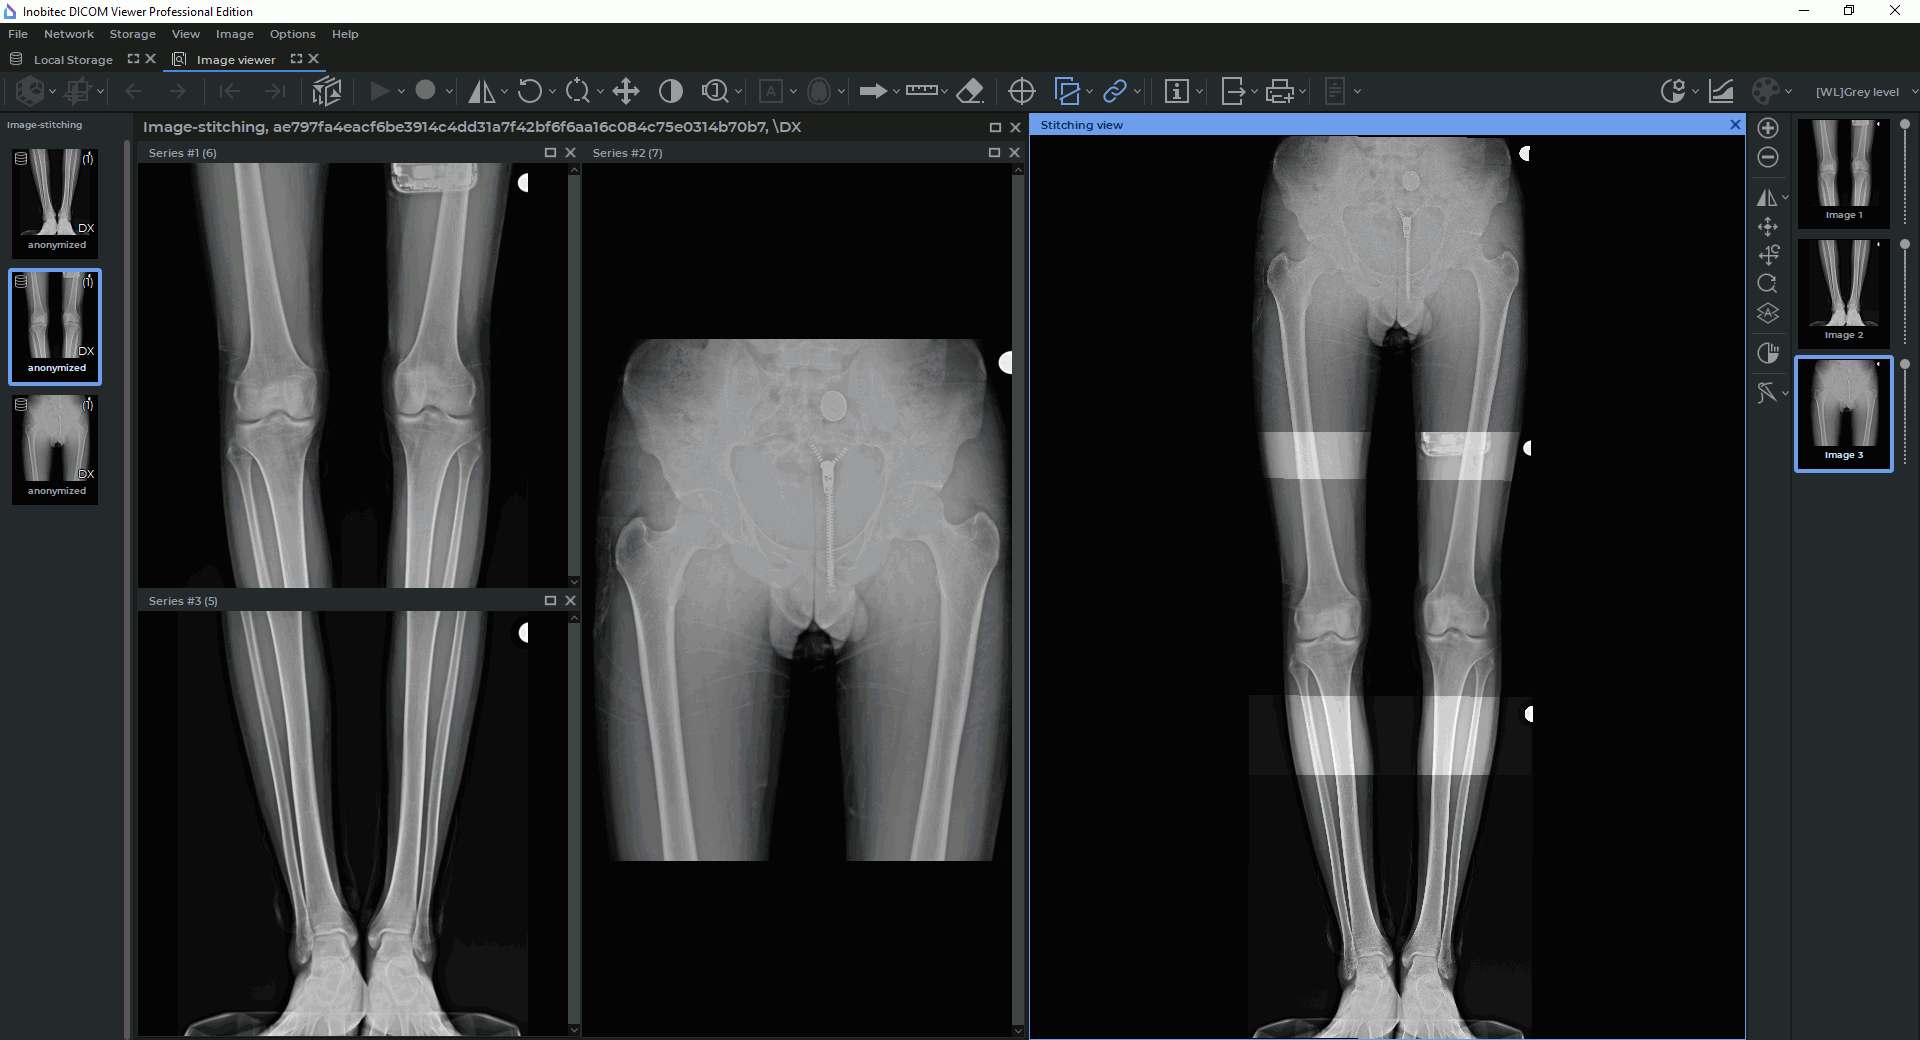

On the right-hand side of the Image viewer tab, the Stitching view window and the image stitching functional toolbar (see Fig. 2.66) will appear. The image from the selected window is automatically added to the Stitching view window. If several images of the series are displayed in the series window, the first image will be added to the Stitching view window.

The image stitching functional toolbar is placed on the right-hand side of the Image viewer tab (Fig. 2.66) and contains:

the Stitching view window where images added for stitching or stitching results are displayed;

a vertical toolbar for working with images in the Stitching view window;

a panel with the list of images added for stitching. The images added to the Stitching view window are shown on the list as thumbnails. The order in which the images were added to the Stitching view window is shown on the thumbnails in the form of numbers. Next to each thumbnail in the Stitching view window, there is an opacity slider for the respective image.